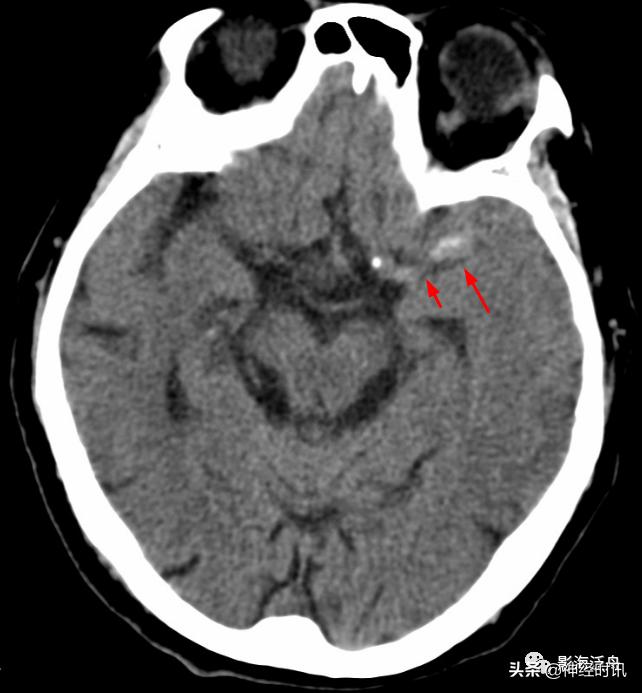

中年女性,骑电动车与人相撞,行头颅CT检查,鞍上池层面可见左侧侧裂池内蛛血(红箭),3天后患者复查头颅CT,左侧侧裂池内蛛血未见明确显示,但同一层面可见右侧天幕区新发蛛血(黄箭)。

通过本病例不难发现少量蛛血的变化是非常迅速的。因此,对于一些可疑的蛛血患者,报告中应建议其短期复查(如24h内)。